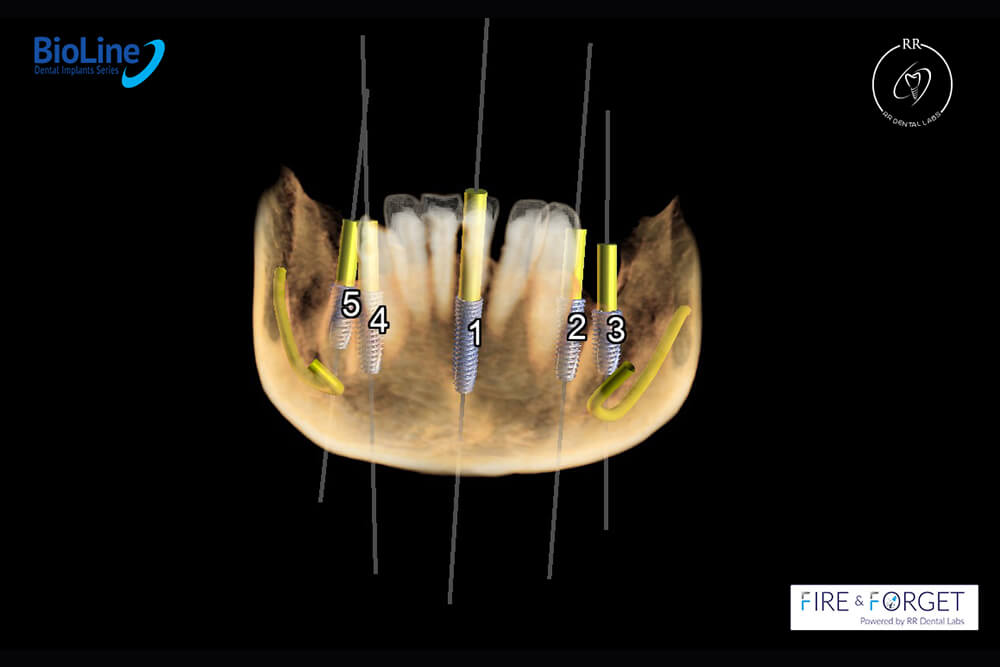

Case 47